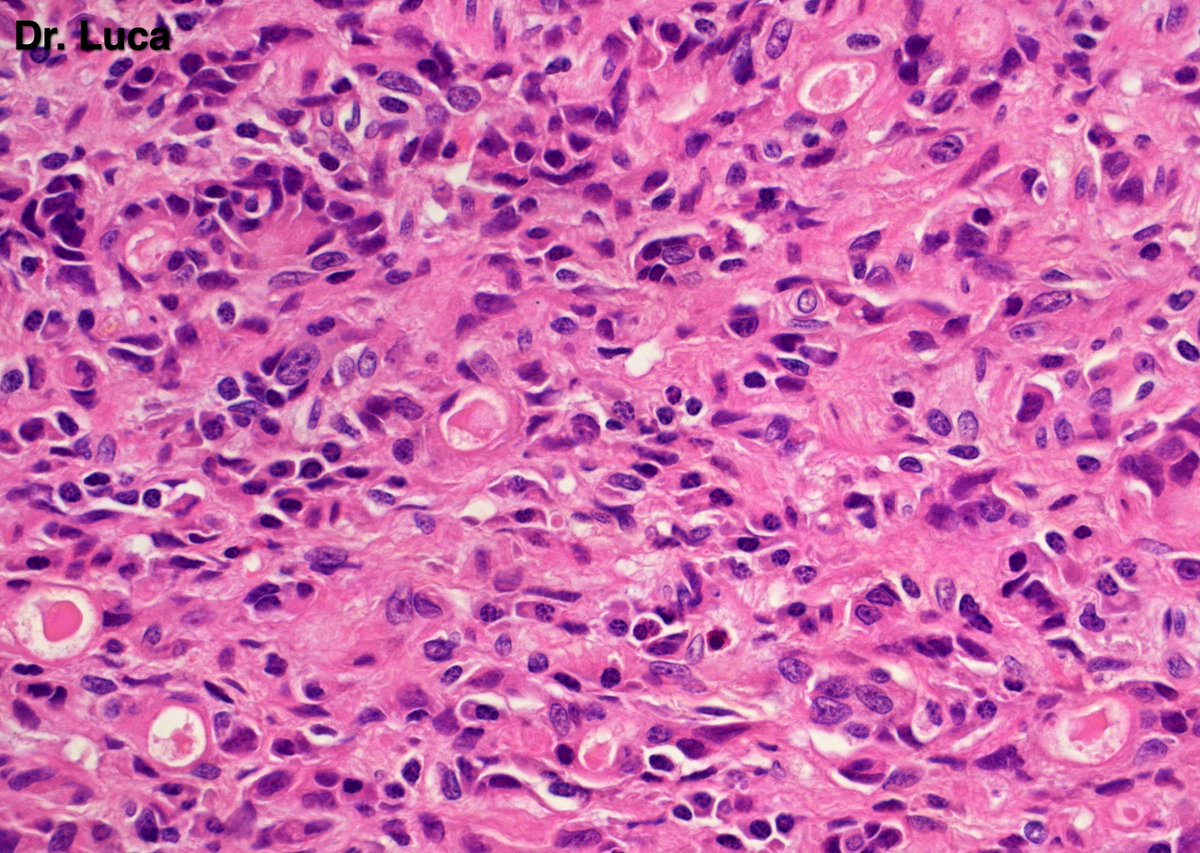

71yoM, bone metastasis, what's your quick H&E diagnosis? (no IHC) @AkgulMd @JPintoPath @slusagar @EKoubaMD @Pathmath1 @s_prendeville @goziemnweke @SumantaDas_7 @D4L14H @PoloniaAntonio @kriyer68 @md_kyle @kis_lorand @MarcosLepeMD @ivanaspath @pathobot #Pathology #PathTwitter

22

25

63